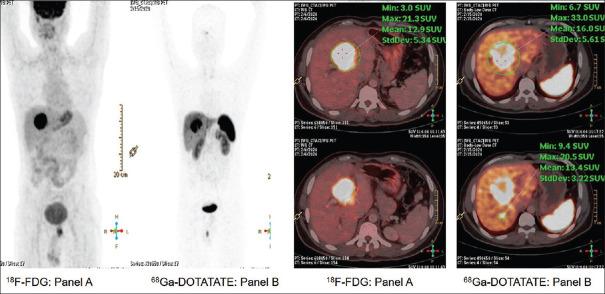

The correlates of dual tracer positron emission tomography and computed tomography (PET-CT) (F-fluorodeoxyglucose [F-FDG] and Ga-DOTATATE) in patients of Grade 3 neuroendocrine neoplasms (NENs) are presented. The first, a patient of gall bladder NEN, operated, with histopathology suggestive of high-grade well-differentiated neuroendocrine tumors with MiB-1 labeling index of 35%, showed uptake with both F-FDG and Ga-DOTATATE, including an uptake equivalent to Krenning score of 3-4 on Ga-DOTATATE PET-CT; in the second, a patient of esophageal NEN, Grade 3 with poor differentiation features, with MiB-1 labeling index of 70%, thereby qualifying for Grade 3 neuroendocrine carcinoma, the FDG uptake was high with minimal uptake on Ga-DOTATATE PET-CT. The illustrations reiterate the impression that relative uptake of Ga-DOTATATE/FDG in the NEN lesions forms a valuable parameter for assessing the dynamic tumor biology in continuum and thus personalizing the treatment strategies.